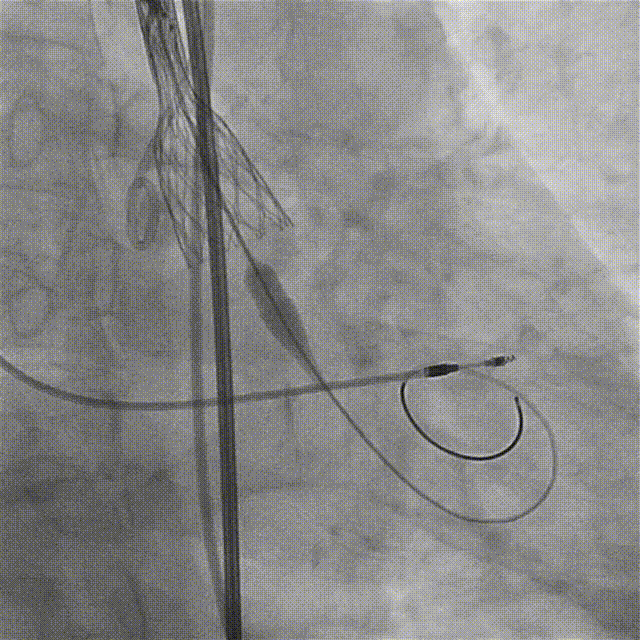

20F大鞘到最狭窄段置入略有阻力

随即轻柔缓慢旋转后成功置入(未保存到影像)

根部造影:可见瓣叶活动僵硬,无反流

18mm球囊预扩,无腰无漏,遂确定选用AV23瓣膜

AV23瓣膜初始定位,瓣上1mm

180bpm起搏下,配合导丝张力,瓣膜稳定释放至工作位